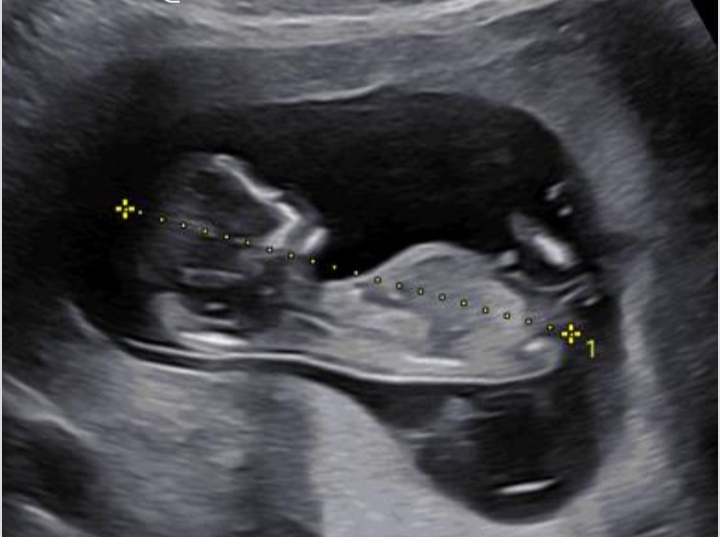

دروغ چرا، منم😁الهی هرچی هست صحیح و سالم بیاد بغلمون 🥲😘ایشالا همونی بشه که دلمون میخواد

ایشالا عزیزم به سلامتی و دل خوش😍😍😍سالم باشه و پسر